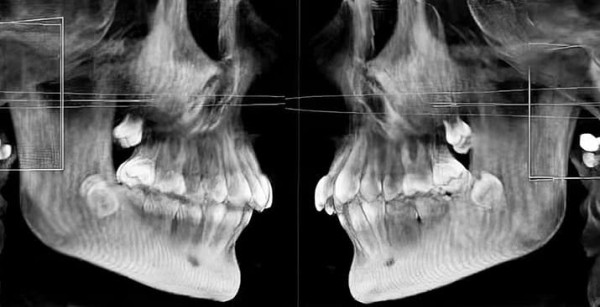

— Конусно-лучевая компьютерная томография сейчас является доступным исследованием, при этом очень информативным, — отметил Яков Тимчук. — И если, например, перед вами пациент, у которого уже долго не прорезываются 7-е зубы или одна из «семерок» не прорезывается, в то время как другие все давно на месте, то иногда причиной может быть расположенная рядом «восьмерка» (см. рис. 5, 5а). В таком случае действительно ее следует удалить. Причиной, конечно же, может быть то, что у пациента нет зачатка седьмого зуба, тогда мы тоже увидим это на снимке.

Рисунки 5, 5а. КЛКТ пациента с показанием для удаления зуба 3.8, так как он не дает прорезаться зубу 3.7.